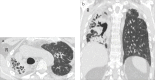

Purpose: Pleuroparenchymal fibroelastosis (PPFE) is a rare form of interstitial pneumonia, characterized by elastotic fibrosis involving the pleura and subpleural parenchyma, predominantly in the upper lobes. PPFE can be either idiopathic or secondary and mostly occurs as a late complication of lung or hematopoietic stem cell transplantation (HSCT). The aim of this study was to evaluate the prevalence of secondary forms in transplant recipients.

Methods: An expert thoracic radiologist retrospectively reviewed high-resolution computed tomography exams of 700 HSCT recipients and 53 lung transplant recipients from the database of the Radiology Department of S. Orsola-Malpighi Hospital dating back from 2007. For each case that radiologically fulfilled PPFE criteria, the following details were retrieved: clinical characteristics, laboratory and functional data, pathologic findings (obtained from one patient) and metabolic data (obtained from three patients).

Results: Six cases clinically and radiologically consistent with PPFE were identified: two HSCT recipients (0.28%) and four lung transplant recipients (7.54%).